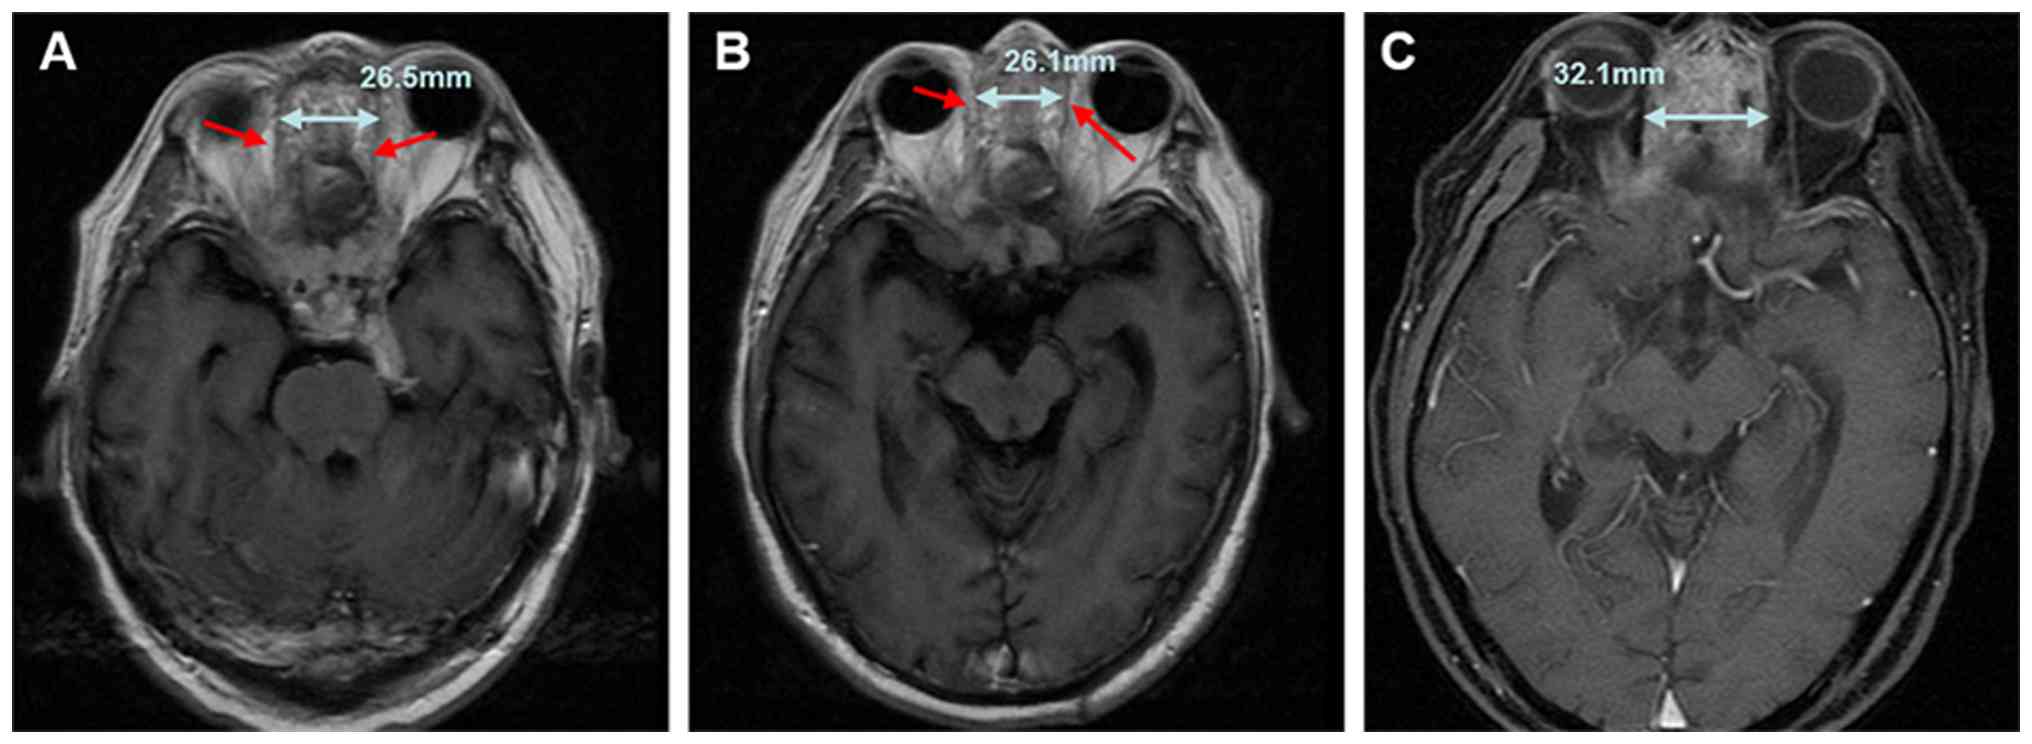

A 60-year-old man presented to West China Hospital, Sichuan University (Chengdu, China) in February 2023 with the primary complaint of progressive loss of vision in the left eye over the past month. Magnetic resonance imaging (MRI) revealed a mass measuring 4.5×2.7 cm located in the region of the ethmoid and sphenoid sinus, with invasion into the intracranial area (Fig. 1). Following a multidisciplinary team discussion, a decision was made to proceed with surgical intervention. The approach selected included a combination of transnasal endoscopy and microscopic craniotomy, accompanied by anterior skull base resection, encompassing the paranasal sinuses, as well as the intracranial and orbital regions. A post-operative pathological analysis indicated the following immunohistochemical findings: CK7(−), CK20(+), CDX2 (+) and villin(+) (Fig. 2), thereby confirming a diagnosis of ITAC. Immunohistochemical staining with CK7, CK20, CDX-2 and villin antibodies (Beijing Zhongshan Jinqiao Biotechnology Co., Ltd.) was performed by the Department of Pathology. Due to the positive surgical margin, adjuvant radiotherapy was administered 2 months later at the General Hospital of Western Theater Command (Chengdu, China). The radiotherapy target volume definitions were as follows: i) Gross tumor volume of the tumor bed (GTV-tb); this encompasses the surgical tumor bed area and any radiographically involved margins visible on imaging. ii) Clinical target volume 1/high-risk clinical volume (CTV-1): This includes the expansion of GTV-tb by 0.5 cm, along with the nasal vestibule, nasal cavity, turbinates and hard palate. However, when the expansion zone approaches critical adjacent structures (such as the optic nerves or cavernous sinus), the margin is reduced to 0.1 cm (Fig. 3). The radiotherapy regimen included a planned dose of 6,480 cGy in 30 fractions (216 cGy per fraction) to the planned GTV-tb (PGTV-tb) [equivalent dose in 2-Gy fractions (EQD2)=65.66 Gy, α/β=10], and 6,000 cGy in 30 fractions (200 cGy per fraction) to the planning CTV-1 (PTV-1) [EQD2=60.00 Gy, α/β=10]. Due to concerns about potential injury to the optic nerve, the patient and their family decided to shorten the radiotherapy course to 25 sessions. The final delivered doses were ~5,400 cGy to the PGTV-tb (estimated EQD2, 54.72 Gy; α/β=10) and 5,000 cGy to the PTV-1. Concurrent chemotherapy was administered with a regimen of cisplatin at 30 mg on days 1–2 every week for four cycles (1 week per cycle).

A soft-tissue mass identified in the

ethmoid and sphenoid sinus of the patient. (A) Axial

contrast-enhanced T1-weighted MRI illustrating the tumor with a

measured diameter of 4.5×2.7 cm. (B) Sagittal contrast-enhanced

T1-weighted MRI demonstrating tumor invasion into the intracranial

area (indicated by red arrows). MRI, magnetic resonance

imaging.

Figure 1.

A soft-tissue mass identified in the ethmoid and sphenoid sinus of the patient. (A) Axial contrast-enhanced T1-weighted MRI illustrating the tumor with a measured diameter of 4.5×2.7 cm. (B) Sagittal contrast-enhanced T1-weighted MRI demonstrating tumor invasion into the intracranial area (indicated by red arrows). MRI, magnetic resonance imaging.